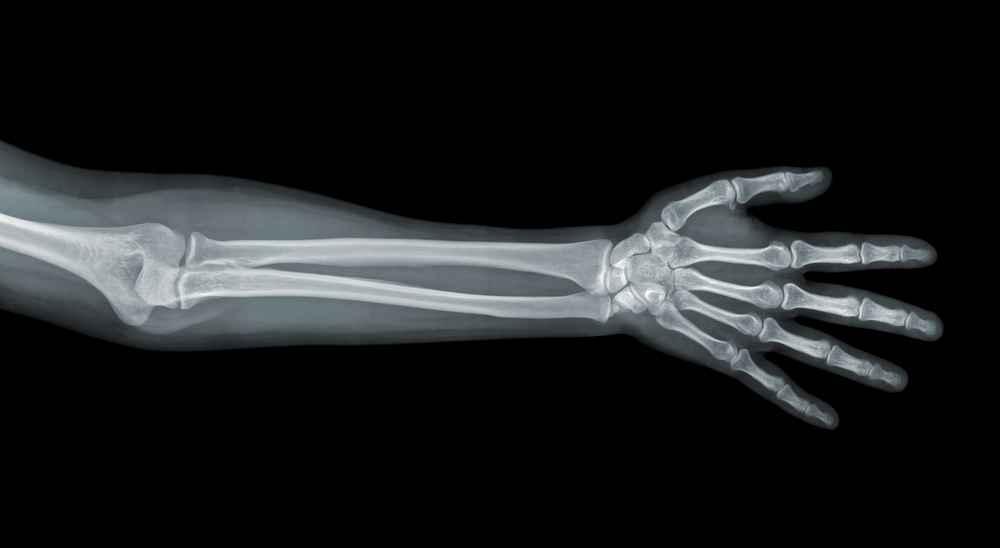

Tulang pengumpil merupakan salah satu bagian tulang yang penting dalam sistem rangka manusia, khususnya pada lengan bawah. Dalam dunia medis, tulang ini dikenal dengan nama radius.

Secara anatomi, tulang pengumpil adalah salah satu dari dua tulang panjang di lengan bawah. Nama tulang yang berpasangan dengan tulang pengumpil adalah tulang hasta (ulna).

Letaknya di sisi lateral (sisi ibu jari) bila tangan menghadap ke atas.

Bentuk tulang pengumpil dapat dijelaskan sebagai tulang panjang yang sedikit melengkung, dengan ujung atas (proximal) dan ujung bawah (distal) yang berbeda bentuk dan fungsinya.

Struktur tulang ini terdiri dari tiga bagian utama, seperti berikut ini.

1. Kepala radius (radial head)

Bagian ini berada di ujung atas tulang (proximal end). Bentuknya bulat dan rata.

Kepala radius terhubung dengan tulang lengan atas (humerus) melalui sendi siku, memungkinkan rotasi tangan seperti membalik telapak ke atas (supinasi) dan ke bawah (pronasi).

2. Leher radius (neck of radius)

Tepat di bawah kepala radius, terdapat bagian yang ramping disebut leher radius. Area ini menjadi tempat melekatnya ligamen yang membantu menjaga kestabilan sendi.

3. Tubuh radius (shaft of radius)

Ini adalah bagian panjang dan utama dari tulang pengumpil. Tubuh radius memiliki bentuk agak melengkung dan bertugas mendistribusikan beban serta menjadi tempat perlekatan otot.

4. Prosesus styloideus radius

Ujung bawah dari radius membentuk bagian penting dari sendi pergelangan tangan. Di bagian ini terdapat styloid process, yaitu tonjolan tulang kecil yang bisa diraba di sisi luar pergelangan tangan.

Ujung distal radius juga berperan penting dalam menghubungkan lengan bawah dengan tulang-tulang kecil pergelangan (karpal).

Struktur tulang pengumpil yang unik ini memungkinkan berbagai gerakan kompleks di tangan dan pergelangan, termasuk rotasi, fleksi, dan ekstensi.